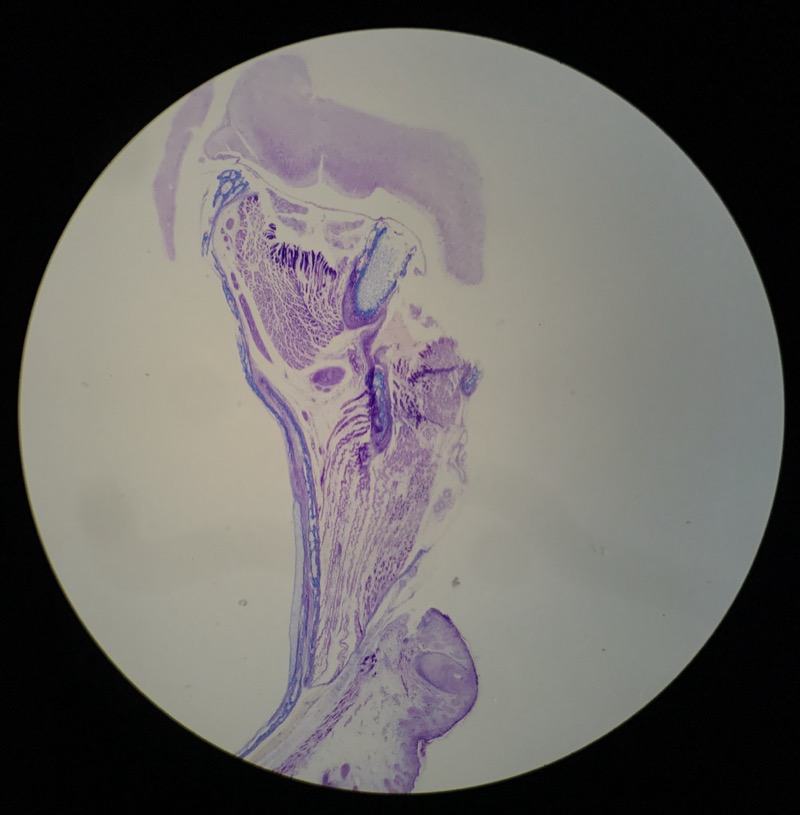

| 1:5:6 | Nagel | ![]() ![]() ![]() ![]() ![]() |